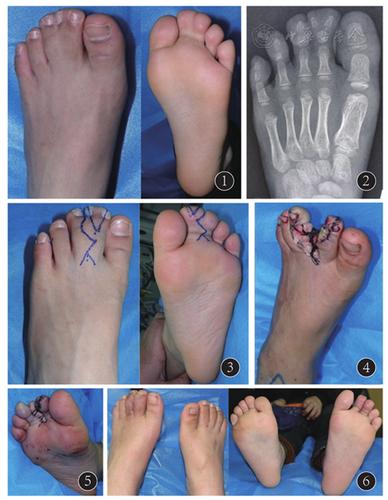

先天性并趾多趾症一例

双手并指,双足多趾伴并趾治疗实例